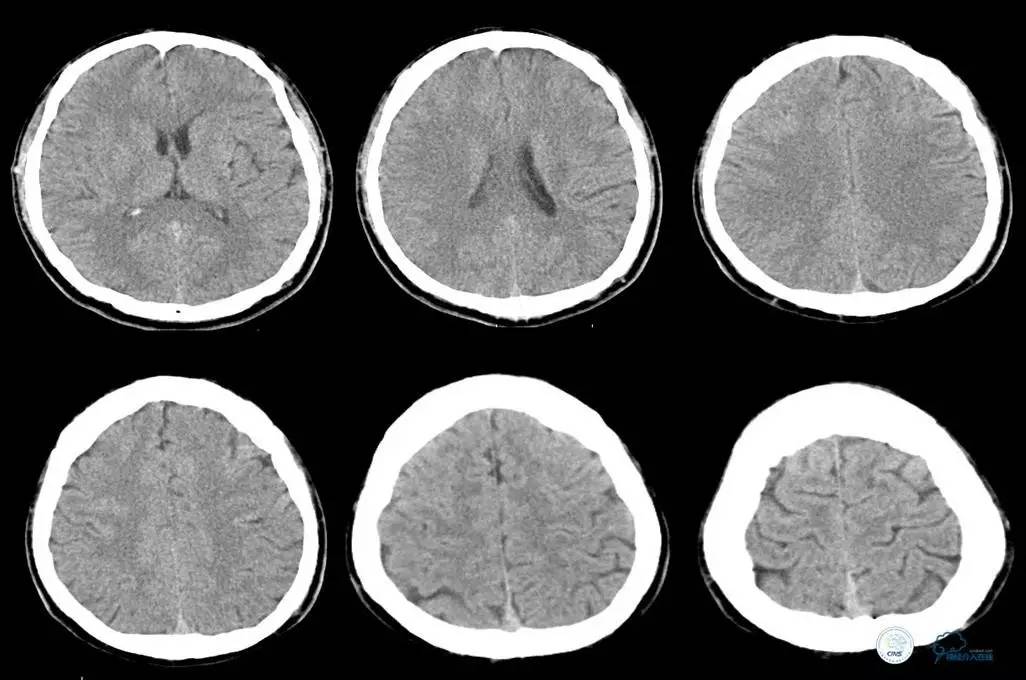

2014年12月16日06时

上级医师急诊查房:神经系统查体同前,四肢血压偏低,85/55mmHg。

诊断:主动脉夹层?

意见:急查主动脉CT。

▼主动脉全程CT

诊断:

主动脉夹层 DeBakey Ⅰ型

短暂性脑缺血发作

急性心肌缺血

急性肾功能不全

急性肠系膜动脉缺血

处理意见:

继续监测血流动力学指标

绝对卧床、强效镇静与镇痛

急请血管外科会诊